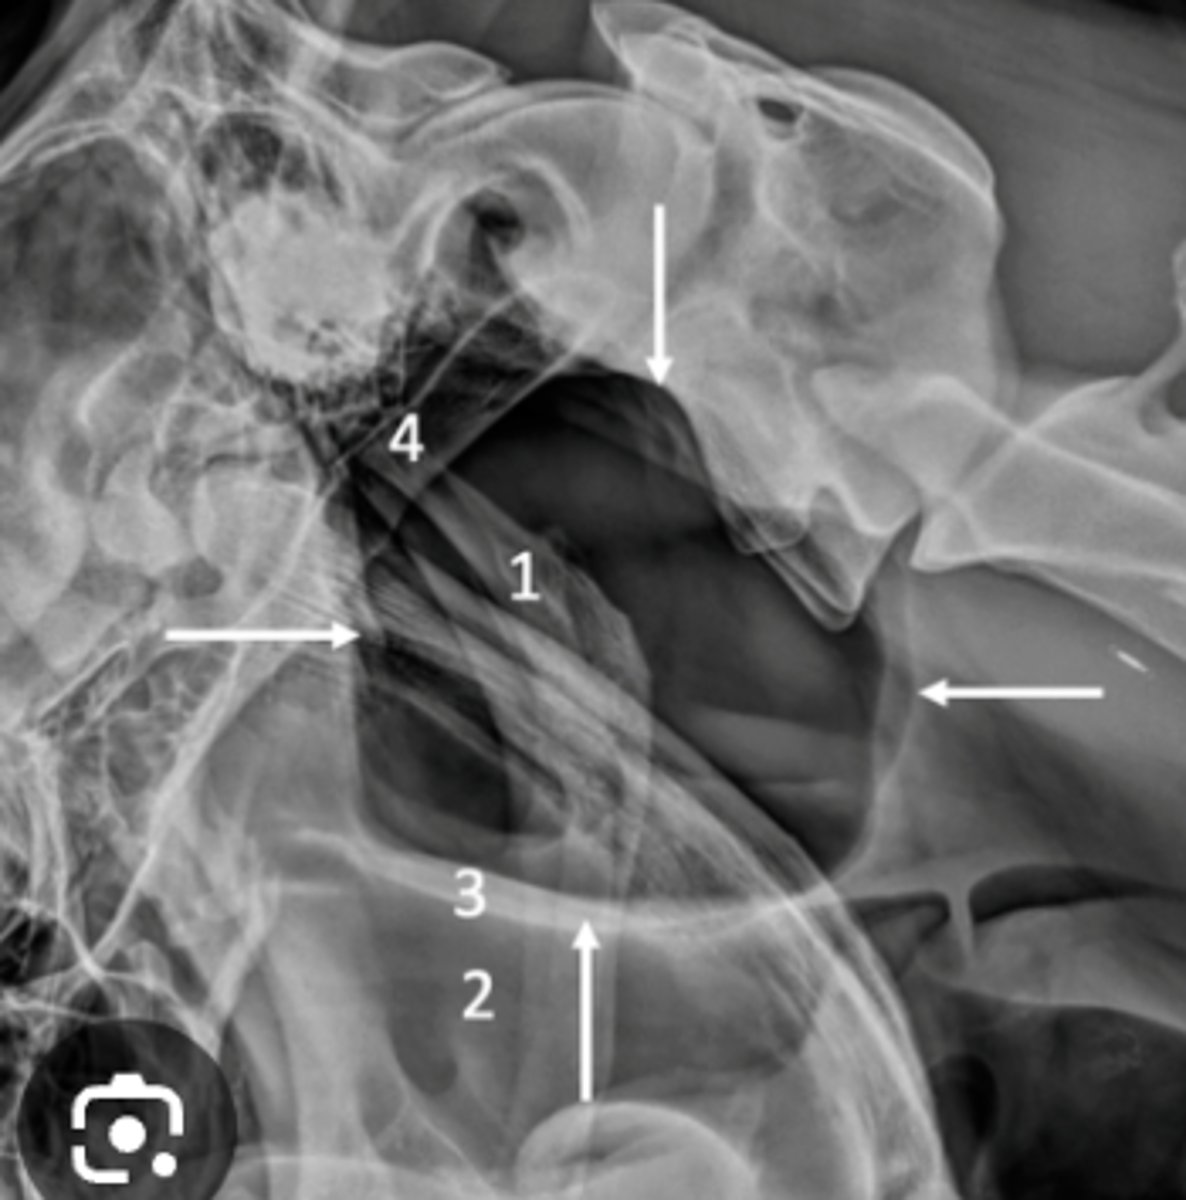

What is wrong with this spine?

narrowed intervertebral space

What is seen in IVDD?